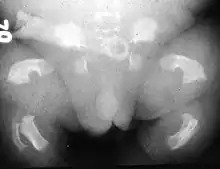

| Radiogram of a baby born with thanatophoric dwarfism | |

Thanatophoric dysplasia is a severe skeletal disorder characterized by a disproportionately small ribcage, extremely short limbs and folds of extra skin on the arms and legs.

Infants with this condition have disproportionately short arms and legs with extra folds of skin. Other signs of the disorder include a narrow chest, small ribs, underdeveloped lungs, and an enlarged head with a large forehead and prominent, wide-spaced eyes. Thanatophoric dysplasia is a lethal skeletal dysplasia divided into two subtypes. Type I is characterized by extreme rhizomelia, bowed long bones, narrow thorax, a relatively large head, normal trunk length and absent cloverleaf skull. The spine shows platyspondyly, the cranium has a short base, and, frequently, the foramen magnum is decreased in size. The forehead is prominent, and hypertelorism and a saddle nose may be present. Hands and feet are normal, but fingers are short. Type II is characterized by short, straight long bones and cloverleaf skull.[1] It presents with typical telephone-handle shaped long bones and H-shaped vertebrae.